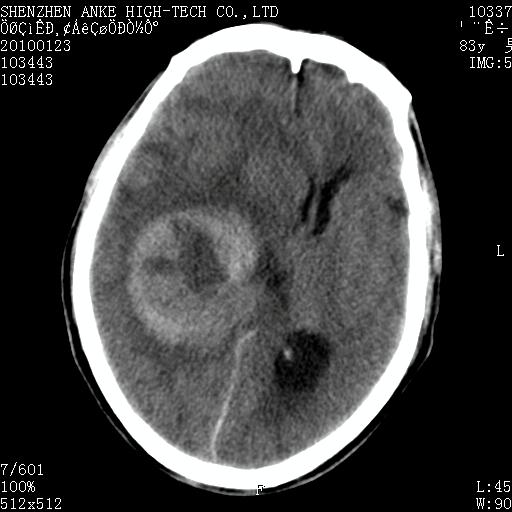

标题: CT24299:头颅平扫

患者:男,83岁,突发意思不清2天。原有脑梗塞病史。

肿瘤卒中,考虑恶性,依次淋巴瘤、转移瘤、恶性脑膜瘤、胶质母等,建议mri。

肿瘤卒中,考虑恶性脑膜瘤可能性大。

考虑脑膜瘤出血.

脑膜瘤多见于老年女性,与雌激素水平有关。本例虽为老年男性,但是本例还是考虑脑膜瘤的可能性大。

镰旁脑膜瘤卒中